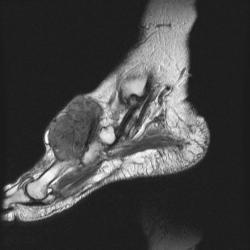

сагиттальная Т2

На серии МР-томограмм получены изображения правого голеностопного сустава.

На тыльной поверхности правой стопы, непосредственно под кожей в области таранной, ладьевидной, клиновидных и оснований от первой до третьей плюсневых костей определяется патологическое образование (тофусы), с распространением на медиальную поверхность стопы, образование неоднородной структуры и МР-сигнала, умеренно гиперинтенсивное на Т1 ВИ, гипоинтенсивное на Т2 ВИ и неоднородного на FAT SAT ИП. Размеры образования 35 х 65 х 40 мм. На постконтрастных изображениях отмечается значительное диффузное усилением интенсивности МР-сигнала от образования. Аналогичные по МР-характеристикам образования, меньших размеров выявляются в левой стопе.

Со стороны костной системы определяются: единичные костно-хрящевые дефекты со склерозом по периферии, диаметром до 3 мм, располагающиеся в субхондральных отделах в области суставных концов большеберцовой и малоберцовой костей, в области прикрепления длинной подошвенной связки к подошвенной поверхности пяточной кости. Множественные дефекты диаметром до 9 мм расположены в области смежных поверхностей ладьевидной и клиновидных костей, некоторые кистовидные дефекты вскрылись в мягкие ткани.

В пяточной кости правой стопы, определяется округлая зона повышенной интенсиновсти МР-сигнала на всех импульсных последовательностях в области блока малоберцовой кости, размерами 7 х 8 мм.

Суставные поверхности уплощены, суставные щели резко сужены, местами определяются краевые костные разрастания.